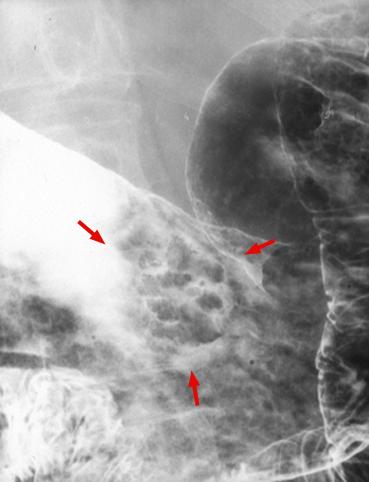

疾患(病理主体)の分類悪性上皮性腫瘍/腺癌

部位(臓器別)胃(部位)/体部

検査方法X-P

腫瘍の肉眼分類0型(表在型)/IIa型(IIa)

病変の最大径(ミリ)15〜19

腫瘍の深達度sm